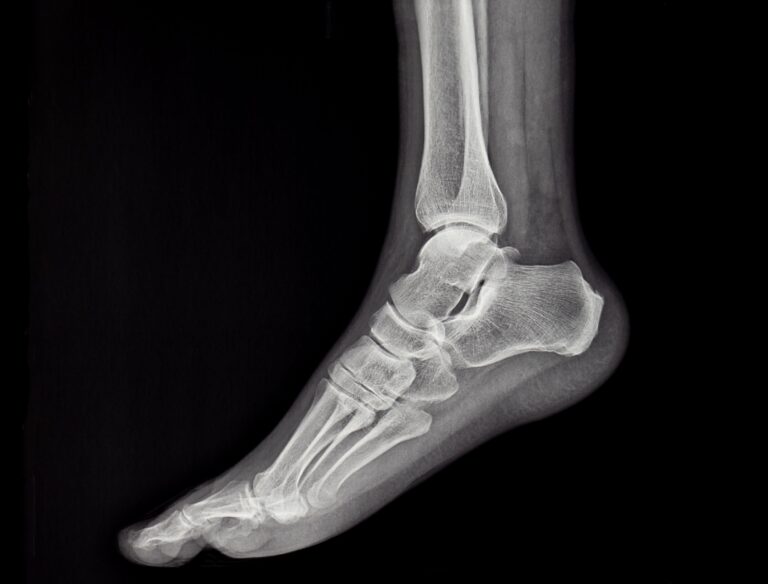

Il y a des parties du corps auxquelles on pense souvent : le cœur, le cerveau, le ventre. Et puis il y a celles qui travaillent dans l’ombre, sans se plaindre, sans bruit, sans réclamer d’attention : les pieds font partie de ces grands oubliés. Ils nous portent dès le matin, quand on se lève encore un peu engourdi. Ils nous accompagnent au marché, à la mosquée, à l’église, à la synagogue, chez les voisins, chez les enfants. Ils nous supportent quand on est pressé, quand on est fatigué, quand on a mal au dos. Et pourtant on ne les regarde presque jamais. Chez la personne vivant avec le diabète, cet oubli peut parfois coûter cher. Non pas parce que le diabète est une punition, mais parce qu’il est une maladie qui aime le silence.

Le diabète ne crie pas toujours. Il ne prévient pas toujours. Il avance doucement, parfois pendant des années, en modifiant peu à peu le fonctionnement du corps. Au niveau des pieds, trois choses importantes peuvent se produire, sans que l’on s’en rende compte :

- D’abord, les nerfs commencent à se fatiguer. C’est un peu comme un fil électrique qui s’use avec le temps : le message passe mal. La douleur devient moins vive, parfois absente. C’est ainsi qu’on ne ressent presque pas une petite pierre dans la chaussure, une couture un peu dure, ou une ampoule.

- Ensuite, le sang circule moins bien. Or le sang, c’est la vie. C’est lui qui nourrit la peau, qui apporte l’oxygène, qui permet la cicatrisation. Quand il arrive difficilement jusqu’aux pieds, la peau devient fragile, sèche, lente à guérir.

- Enfin, les défenses naturelles du corps sont moins efficaces. Une petite plaie qui aurait guéri toute seule chez quelqu’un d’autre peut, chez la personne diabétique, s’infecter, s’aggraver, s’installer.

Et c’est ainsi que, sans douleur, sans grand signal d’alarme, le pied diabétique peut commencer son histoire.